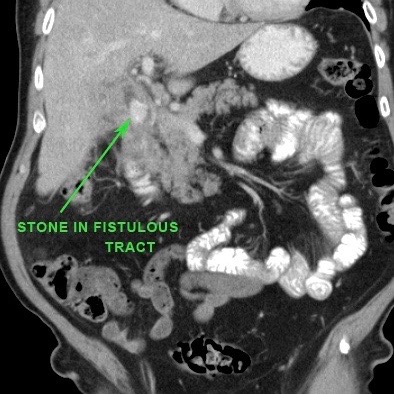

Viêm túi mật không được chẩn đoán hoặc không được điều trị cũng có thể dẫn đến hình thành đường rò vào tá tràng.

Đây là một biến chứng không thường gặp, nhưng khi xảy ra, hầu hết các trường hợp sỏi sẽ di chuyển vào ruột non, nơi sỏi bị kẹt lại và gây ra tắc ruột do sỏi mật.

Trong các trường hợp hiếm gặp của rò tá tràng, một viên sỏi mật lớn có thể bị “kẹt” tại đường rò vào tá tràng.

Do mô viêm và mô xơ thứ phát, tình trạng này có thể dẫn đến hẹp và tắc nghẽn.

Tình huống đặc biệt này được gọi là “hội chứng Bouveret” với biểu hiện lâm sàng chính là tắc nghẽn đường ra dạ dày.

Trong các trường hợp hiếm gặp của rò tá tràng, một viên sỏi mật lớn có thể bị “kẹt” trong quá trình rò kéo dài.

Do mô viêm và mô xơ thứ phát, tình trạng này có thể dẫn đến hẹp và tắc nghẽn tá tràng.

Tình huống đặc biệt này được gọi là “hội chứng Bouveret” với biểu hiện lâm sàng chính là tắc nghẽn đường ra dạ dày (hình).

Một viên sỏi lớn bị “kẹt” trong đường rò từ túi mật biến dạng đến tá tràng.

Dày thành tá tràng thứ phát (đầu mũi tên) cùng mô viêm và mô xơ xung quanh gây ra tình trạng ứ đọng dạ dày từng đợt kèm nôn mửa.